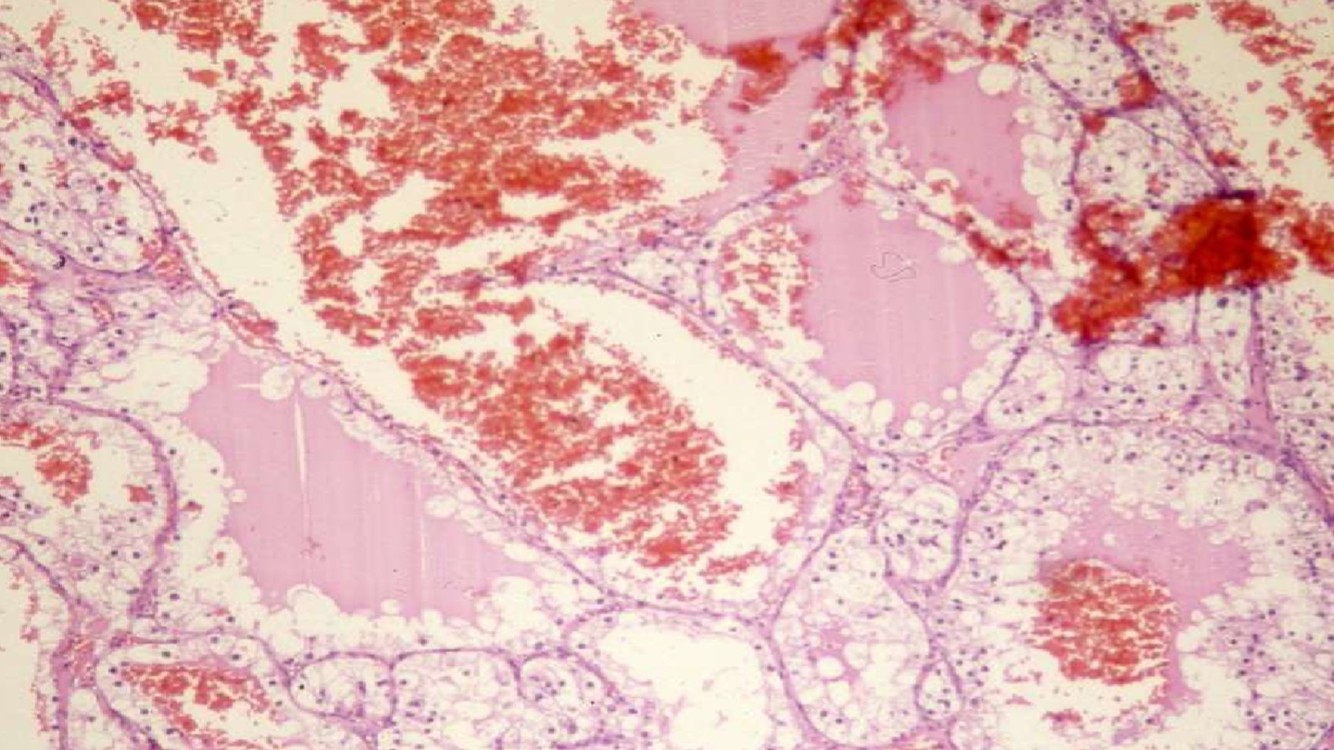

XANTHOGRANULOMATOUS PYELONEPHRITIS

- Often associated with large staghorn calculi of renal pelvis

- Many of these patients may have UTI, secondary to E. coli or Proteus

- May presents as a mass-like lesion